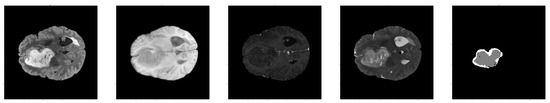

2.1. Data

We utilized the Brats 2021 dataset [1,2,16] for our study. This dataset comprises multi-parametric MRI scans of glioma patients, featuring four modalities: T1-weighted, T1 with contrast enhancement, T2-weighted, and FLAIR (see Figure 2). These provide varied insights into brain anatomy and tumor characteristics. It includes segmentation labels for tumor sub-regions (necrotic core, edema, enhancing tumor, whole tumor). The data are co-registered, isotropically resampled, and skull-stripped for consistency across scans [2].

Figure 2. T1-weighted, T1 with contrast, T2-weighted, FLAIR sequences, and a tumor segmentation mask.